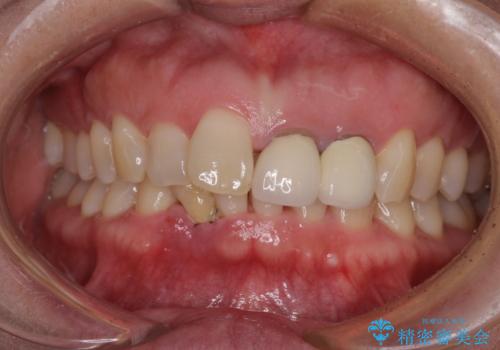

- 下顎前歯が抜けそうとのことで来院された患者様です。

初診の状態ではすぐにでも抜けそうな状態で、インプラントによる補綴治療を行うこととしました。

インプラント治療に際し、前歯の叢生に対する矯正治療を提案したところ、興味を持たれたので、インビザライン・ライトによる矯正治療を行うこととしました。

抜歯後にスペースができると恥ずかしいため、抜歯した歯を接着剤で固定した上で矯正治療を行い、その後インプラントやオールセラミッククラウンの装着を行うこととしました。